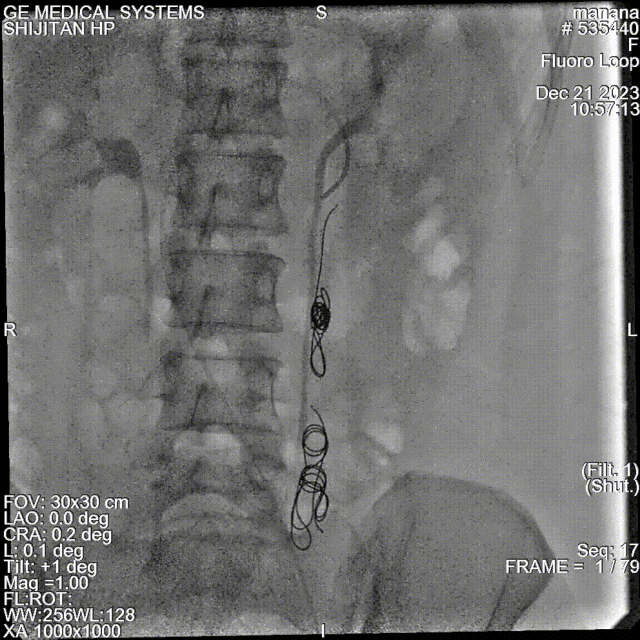

★ 卵巢静脉造影(诊断金标准)

尽管是侵入性操作,但静脉造影仍是诊断的“金标准”。其诊断标准(2019UIP)包括:

卵巢静脉直径 > 6 mm;

造影剂在盆腔静脉丛滞留 > 20秒;

盆腔静脉丛充血、迂曲,造影剂反流可越过中线;

可见同侧或对侧髂内静脉、外阴、阴道及大腿静脉曲张显影。

反流性疾病:卵巢静脉和/或髂内静脉反流——建议行卵巢静脉栓塞(Ⅱa B级推荐)。但需注意,部分患者合并髂内静脉反流,需一并处理。